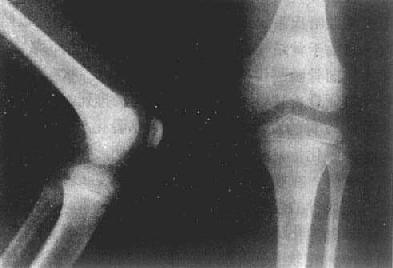

图2-1-2 儿童正常膝关节

(一)小儿骨骼 长骨是软骨雏型经骨化形成的,一般有3个以上的骨化中心,一个在骨干,另外的在两端。前者为原始或一次骨化中心,后者为继发或二次骨化中心。原始骨化中心在胚胎第5周后在骨干中央发生,骨化迅速进行。出生时,长骨骨干已大部骨化,只两端仍为软骨,即骺软骨(epiphyseal cartilage)。因此,小儿长骨的主要特点是骺软骨,且未完全骨化。可分为骨干(diaphysis)、干骺端(metaphysis)、骺(epiphysis)及骺板(epiphyseal plate)等部分(图2-1-1、2)。

3.骺 为长骨未完成发育的一端。在胎儿及儿童时期多为软骨,即骺软骨,X线片上不显影。骺软骨有化骨功能。在骨化初期于骺软骨中出现一个或几个二次骨化中心。X线表现为小点状骨性致密影。骺软骨不断增大,其中的二次骨化中心也不断由于骨化而增大,形成松质骨,边缘由不规则变为光整。

4.骺板(骺盘) 当骺与干骺端不断骨化,二者之间的软骨逐渐变薄而呈板状时,则称为骺板。因为骺板是软骨,X线片上呈横行半透明线,居骺与干骺端之间,称之为骺线(epiphyseal line)。骺板不断变薄,最后消失,即骺与骨干结合,完成骨的发育。X线表现为骺线消失。